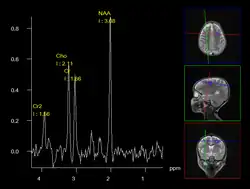

A less intrusive alternative imaging technique is magnetic resonance spectroscopy (MRS), which is used to determine the chemical compositions of cells. However, it is not as reliable as biopsies.[12]